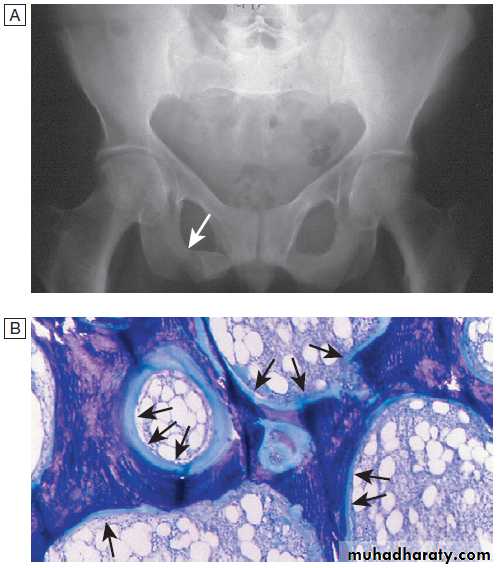

Pathological changes in osteoarthritis.

A Abnormalnests of proliferating chondrocytes (arrows) interspersed with matrix devoid

of normal chondrocytes.

B Fibrillation of cartilage in OA.

C Radiograph

of knee joint affected by OA, showing osteophytes at joint margin (white arrows), subchondral sclerosis (black arrows) and subchondral cyst (open arrow).